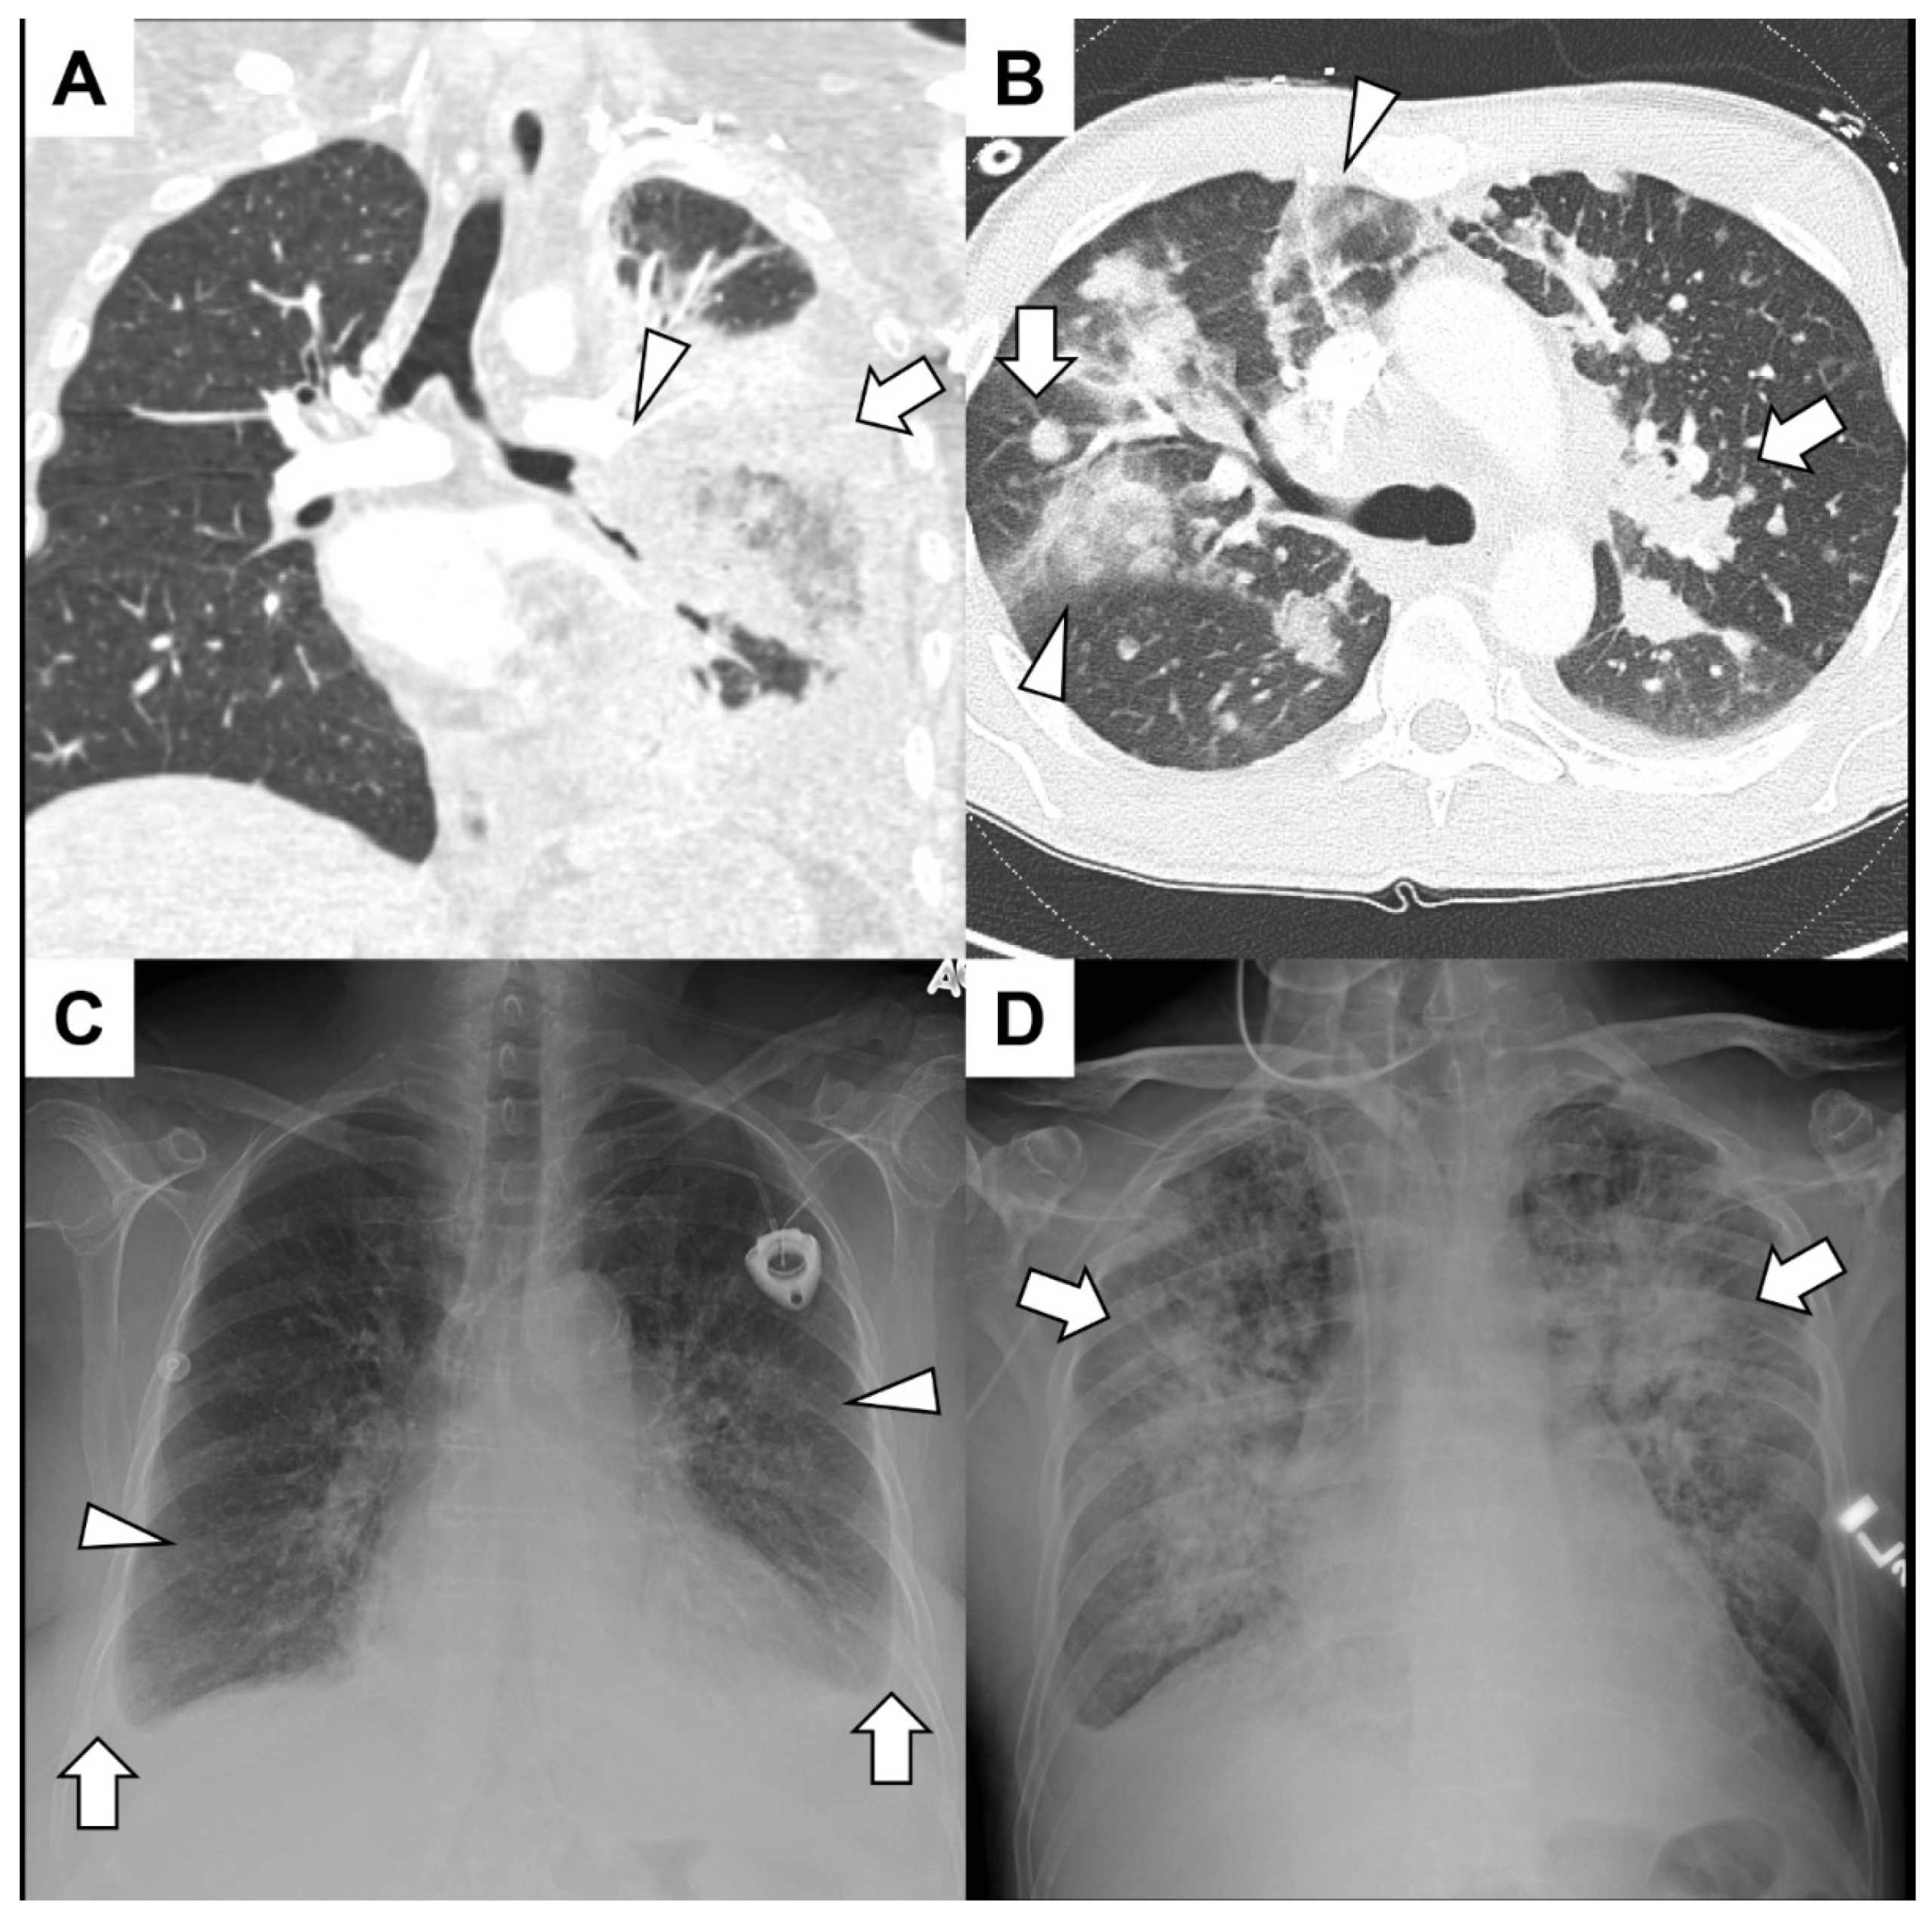

1. Rontgen dada untuk melihat apakah ada cairan atau sumbatan di paru. As a result, gambar rontgen bisa menunjukkan kelainan di dalam rongga dada

2. CT scan yang memberi gambar lebih rinci tentang kondisi di dalam dada. Furthermore, tes ini bisa mengungkap beberapa penyebab hemoptisis

3. Bronkoskopi yaitu pemeriksaan dengan selang kamera lewat hidung atau mulut. Also, dokter bisa melihat langsung kondisi saluran napas dari dalam